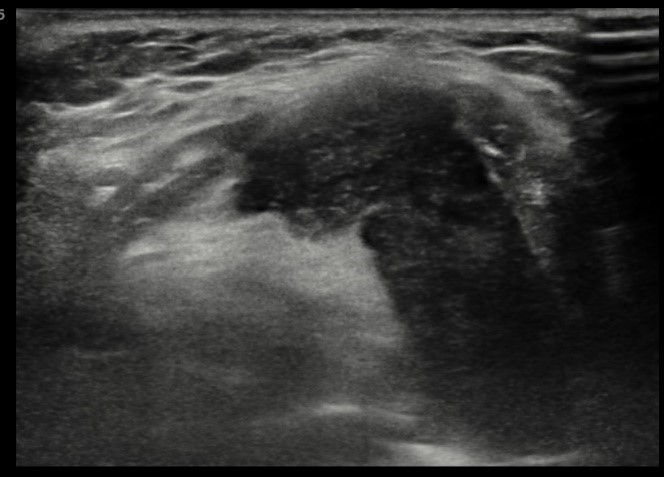

The lesion was readily visualized on ultrasound (Figures 4 and 5).

![]() |

Figure 5. Transverse image |